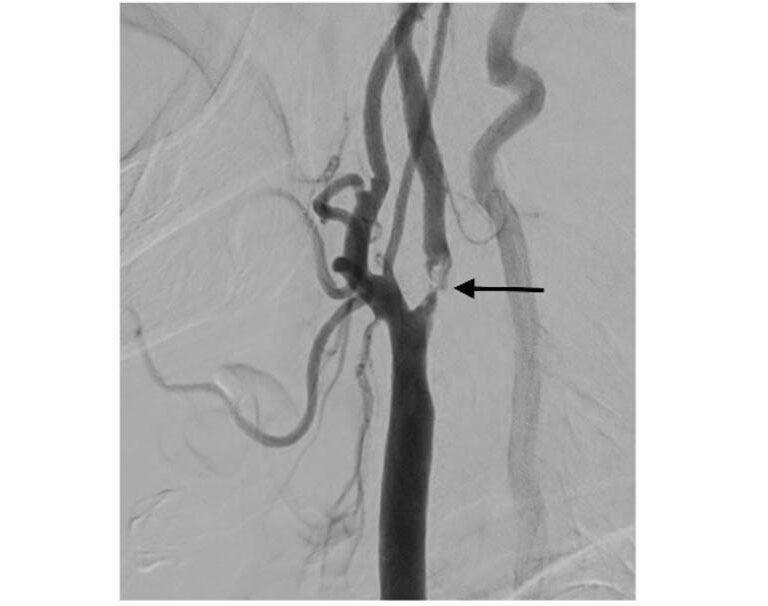

در موارد شدیدتر یا زمانیکه خطر سکته بالا باشد، بهترین گزینه درمانی آنژیوپلاستی کاروتید و استنتگذاری توسط دکتر سید محسن جهرمی مقدم است.

در این روش غیرتهاجمی، از طریق شریان کشاله ران یک لوله باریک (کاتتر) به سمت شریان کاروتید هدایت میشود. بالون کوچک در انتهای آن باد شده و مسیر تنگ شریان باز میگردد، سپس فنر یا استنت فلزی برای باز نگه داشتن رگ قرار داده میشود.